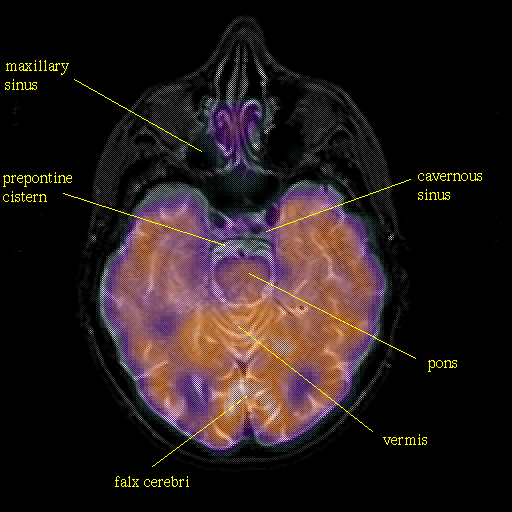

Pointers

Labeled